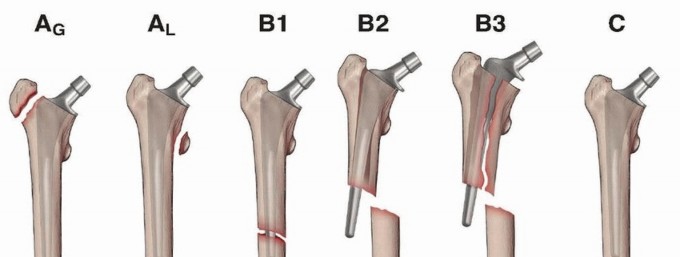

DEFINITION Fractures that occur above or around the femoral component of a total knee arthroplasty (TKA). The…